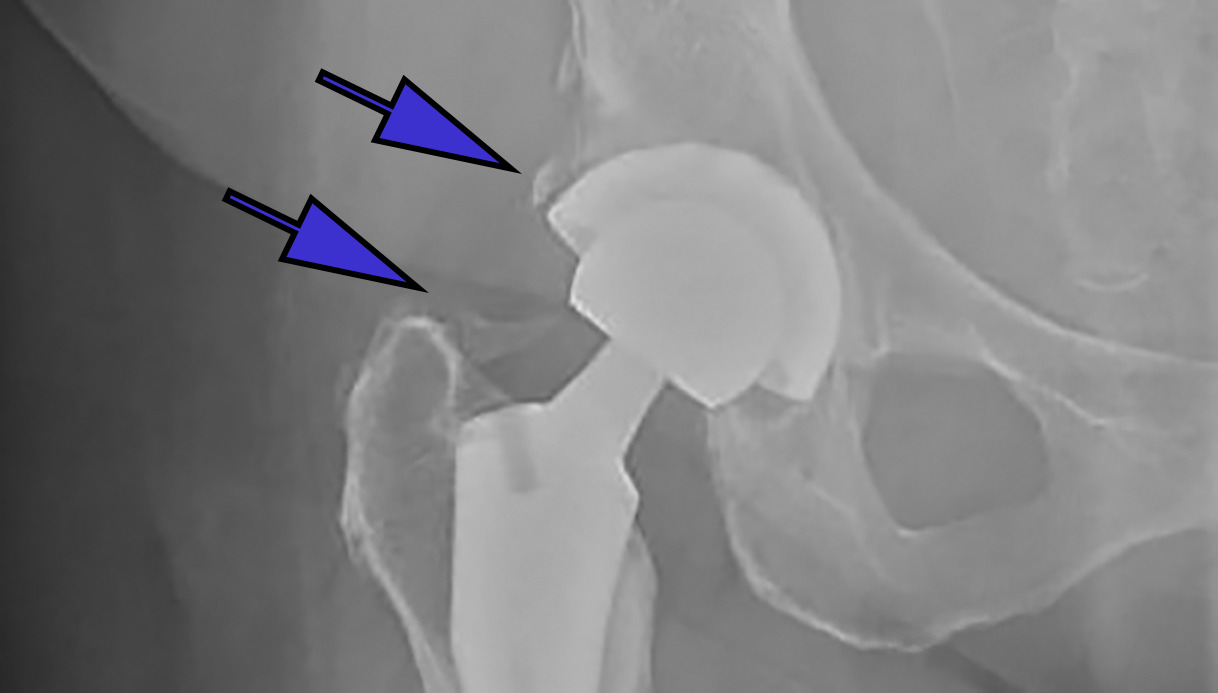

A manual medical record review was conducted by three upper level residents (PK, RD, SY) to investigate if administration of a NSAID was administered during the hospital stay; specifically, both drug type and dose were recorded. DVT prophylaxis, specifically the dose of ASA, was also recorded. Finally, HO was conducted by one senior resident (first author PK), using the Brooker Classification System.18 (Figures 1a-1c) Observing this system, Class 1 is described as islands of bone within the soft tissues about the hip. Class 2 includes bone spurs originating from the pelvis or proximal end of the femur, leaving at least 1 cm. between opposing bone surfaces. Class 3 consists of bone spurs originating from the pelvis or proximal end of the femur, reducing the space between opposing bone surfaces to less than 1 cm. Class 4 shows apparent bone ankylosis of the hip.19 Finally, if post-operative complications such as dislocation occurred this was included in our review of the EMR.